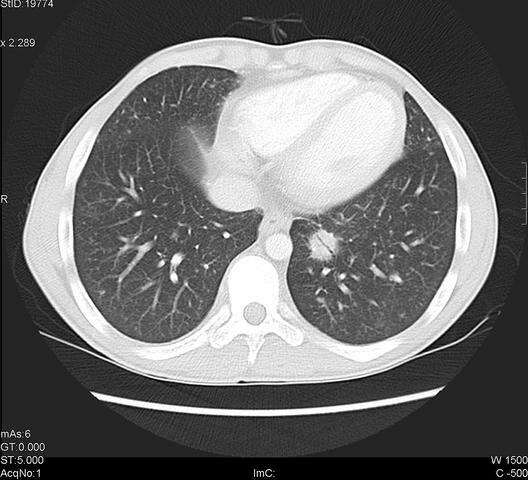

Aparecieron la tomografía de segunda generación y el número de detectores aumentó a 30 y el tiempo de adquisición de datos disminuyó a 20 segundos y se utilizó para estudiar tórax y abdomen